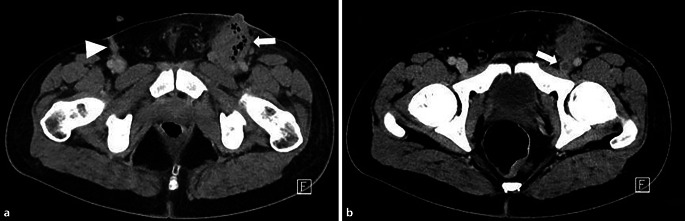

Abstract Image